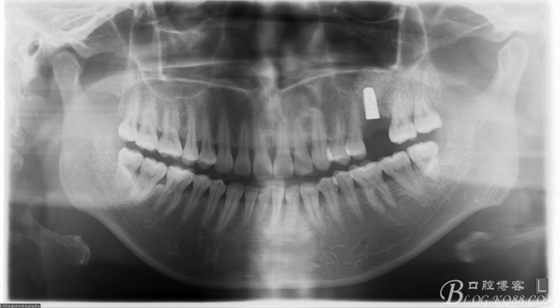

術(shù)后X片。